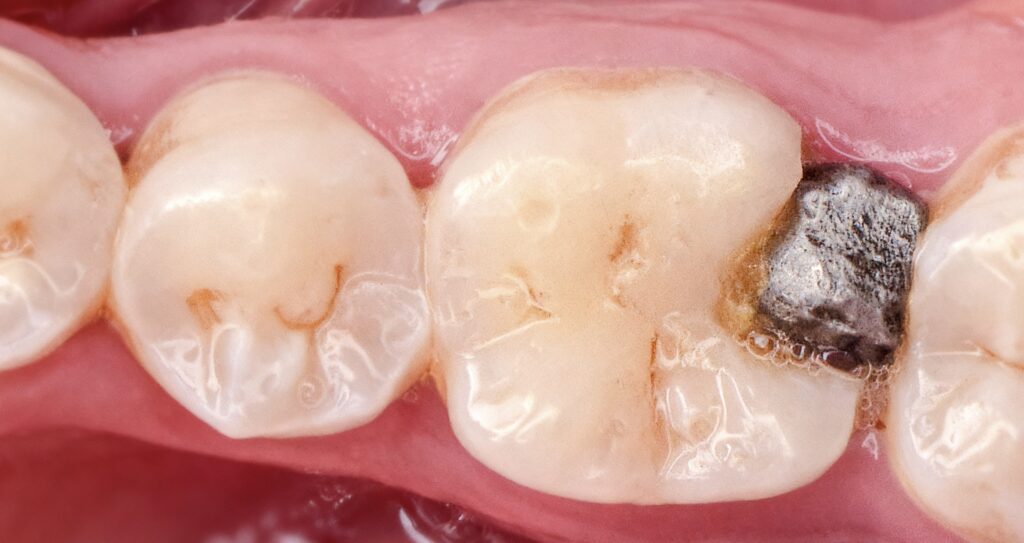

A patient presented with discomfort in posterior teeth. Clinical examination revealed:

- Defective amalgam restoration with marginal breakdown

- Recurrent caries adjacent to the restoration

- Occlusal and proximal carious lesions in molars

The findings indicated the need for amalgam replacement and caries management.

- Identification of failed amalgam restoration

- Detection of secondary (recurrent) caries